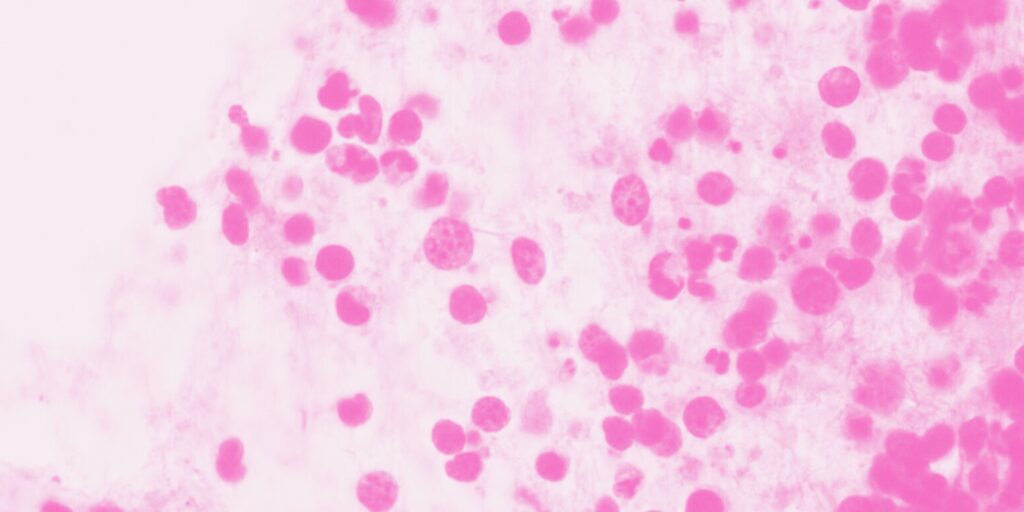

Mesothelioma Cancer

Mesothelioma Cancer Mesothelioma is a rare and serious cancer that affects the mesothelium, or lining, of various organs. You are at risk of developing this cancer if you have been exposed to asbestos. There is a 20-40 year latency between exposure and cancer development. Every year, there are approximately 3,000 new cases of mesothelioma in the United […]